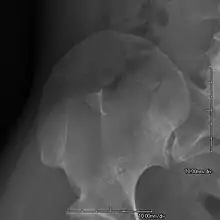

- Exostoses arising from the posterior aspect of the iliac bones ("iliac horns") are present in as many as 80% of patients; this finding is considered pathognomonic for the syndrome.

An elbow of a man with nail–patella syndrome (NPS)

This is a view from a different angle of the same man's other elbow